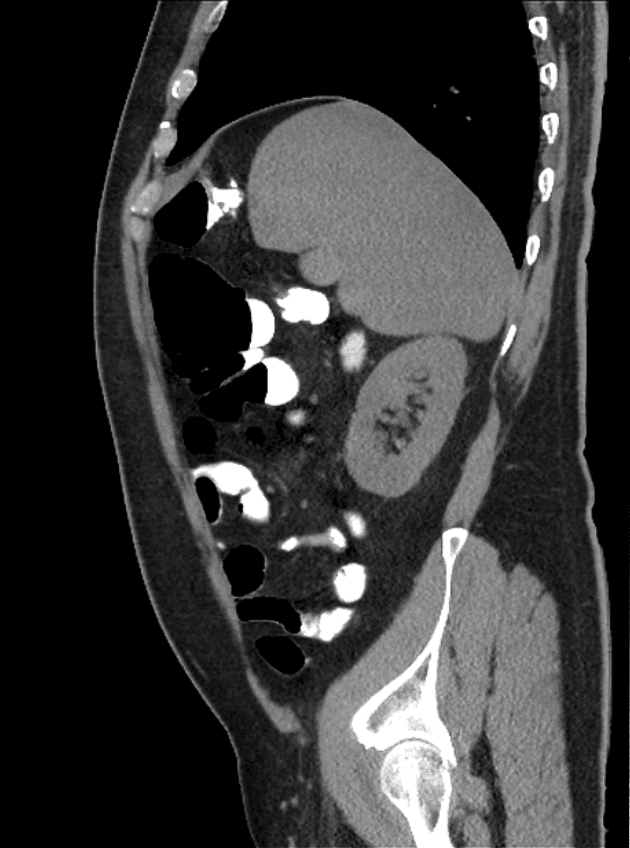

Chilaiditi

Chilaiditi - Ảnh 3

» Thông tin: Nam giới – 48 tuổi.

» Lâm sàng: Đau mạn sườn phải 1 tháng.